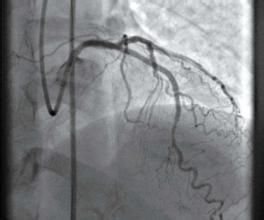

三支病變 triple vessel disease

定義所謂三支病變,就是三支血管,右冠狀動脈、左冠狀動脈前降支、左冠狀動脈迴旋支都發生比較嚴重的病變。

治療冠心病三支病變患者,一般都是建議外科搭橋,也就是冠狀動脈旁路移植的適應症,如果硬要做介入手術,價格也不便宜,而且即刻效果 和長期效果 都不理想。因此是建議首選外科搭橋。冠狀動脈一共就三個主要分支,介入是將球囊導管放入病變血管,那么球囊擴張時本身也是暫時阻斷 血流供應的,那么這樣對心臟的危險比較大。如果是用不用球囊,用直接的自膨脹支架,考慮病變比較嚴重有時自膨脹支架未必就一定能夠擴開血管。

另外支架本身也是異物,放置進去也是容易支架內再狹窄,儘管現在想了各種辦法,但是如果多支血管病變,再狹窄的幾率肯定大大增加的。 從價格上三支都狹窄,那么 支架的價格也可能更高。

介入手術,此時不是首選的,但是如果外科搭橋有禁忌症,那么退而求其次,還是可以考慮介入手術的 。

所謂搭橋,冠狀動脈旁路移植,就是某一支或者某幾支冠狀動脈發生嚴重問題,另外從身體其他部位,取下相對不重要的血管(比如內乳動脈、大隱靜脈等)來移植上去。而冠狀動脈介入手術,那么是對於某支血管中最狹窄的部分擴張一下,用一個支架支撐。